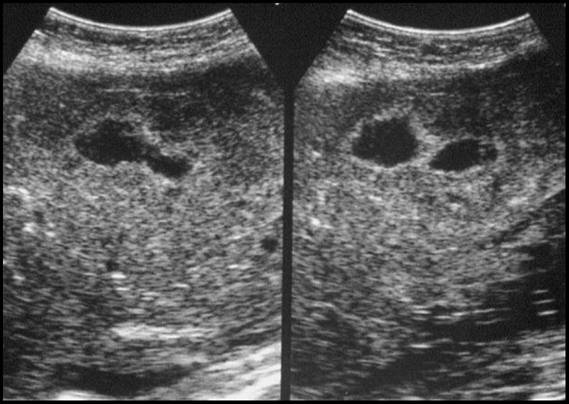

Question : Rôle de l’échographie dans le diagnostic du cancer de l’endomètre ?

Dr BOUMEHDI Bounhir : Dans le cancer de l’endomètre (L'endomètre est le revêtement intérieur de la paroi du corps de l'utérus, la partie de l'utérus où se déroule la grossesse), la circonstance de découverte le plus fréquente est la survenue de métrorragie, avec un pic de fréquence entre 55 et 65 ans. L’échographie endo-vaginale joue un rôle capital dans son diagnostic, elle permet d’évaluer l’épaisseur de l’endomètre et poser l’indication d’une biopsie qui permettra de confirmer le diagnostic et de déterminer le type histologique. Une fois le diagnostic posé, l’IRM joue un rôle fondamental dans la planification du traitement en précisant l’extension au myomètre (muscle utérin avec ces différents niveaux), l’extension ganglionnaire, et aux organes de voisinage.